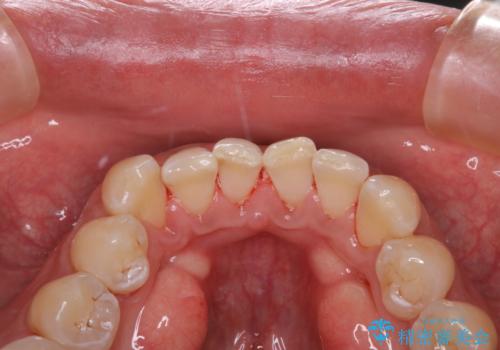

1年ぶりにコーヒーによる着色落とし PMTC